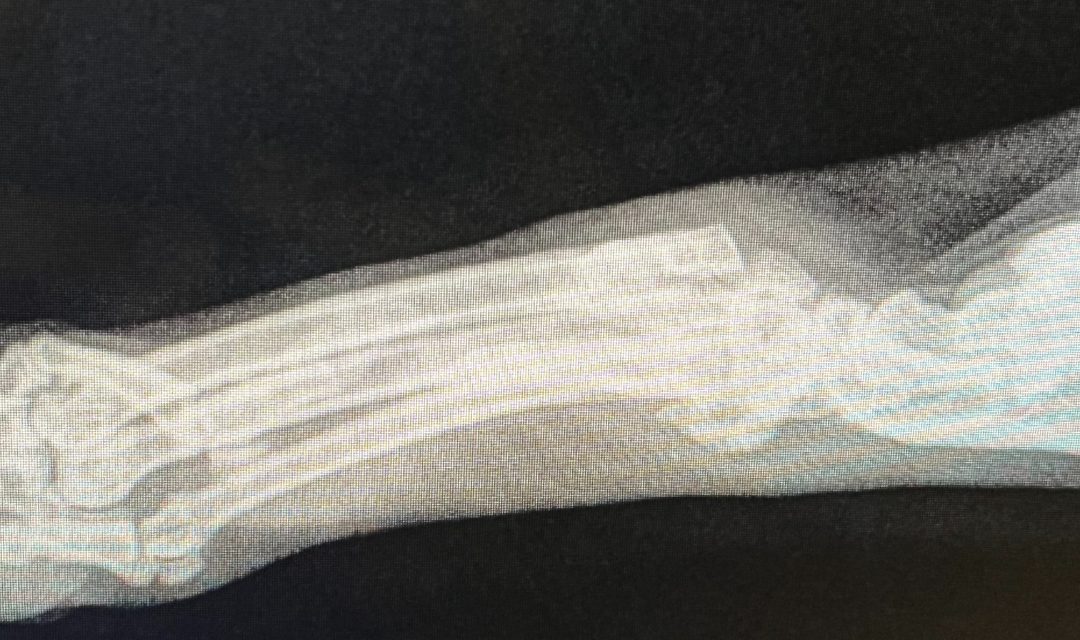

Margaret came to us from Clayton (Johnston County) with an enlarged hind leg. Poor Margaret was in so much pain that she struggled to use that leg. Upon her arrival at SAFE Haven, she received an exam and x-rays, which revealed Queen Margaret was suffering from severe bone degeneration in her lower limbs.

The Medical Director of the SAFE Care Spay/Neuter Clinic, Dr. Tiffany Kutner, had a couple of thoughts on what this degeneration could mean. She was concerned that Margaret had cancer in her leg or an old, very severe injury causing infection of her leg. Either way, Queen Margaret was in extreme pain, and the best way to ensure her survival was to amputate her leg.